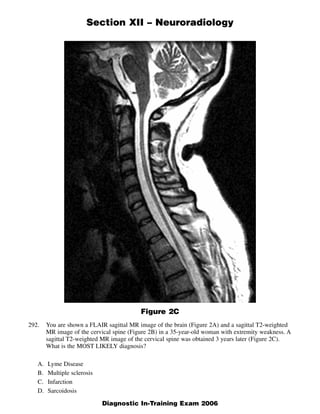

The document discusses several radiology cases involving the brain and spine. Question 291 presents CT scans of a woman with headaches and asks for the most likely diagnosis of a fat-containing extraconal orbital mass. Question 292 shows MR images of a woman with extremity weakness and asks for the most likely diagnosis of multiple brain and spine lesions. Question 293 presents MR images of a man with back pain and asks for the diagnosis of a posterior spinal mass seen on the images.